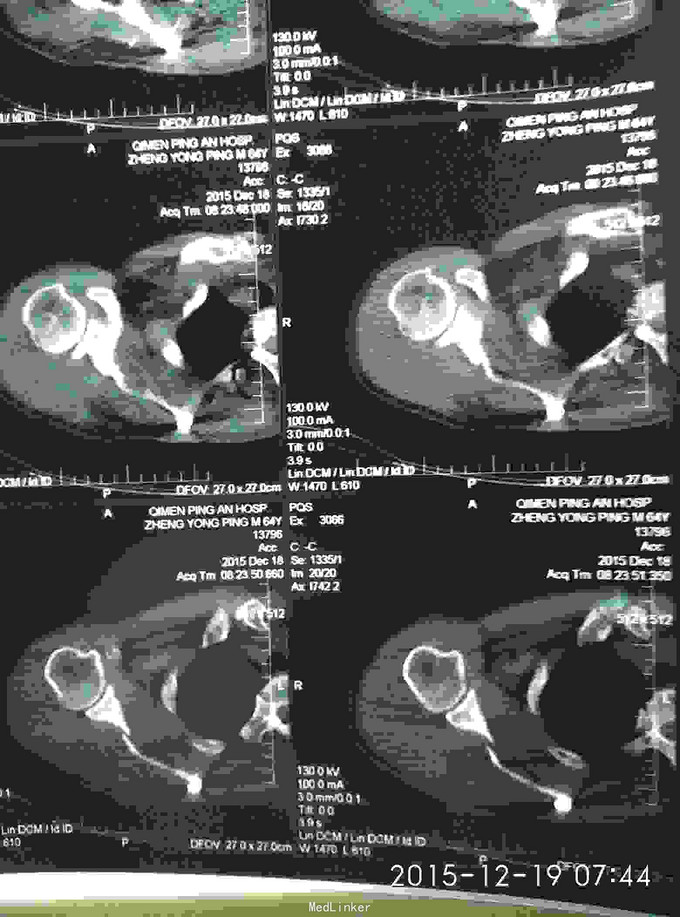

右肩峰及肩胛骨骨折

骨折 肩峰骨折 肩胛骨骨折

外伤致右胸疼痛及右肩疼痛,活动受限1天入院。去年右肩胛骨骨折在外院行切开复位内固定术。

胸廓挤压试验阳性,右肩峰压痛阳性,右肩主动活动受限,外展约30度。x片及CT示右肩峰骨折及肩胛骨骨折,右第6.7.8.9肋骨骨折。

右肩峰骨折,右肩胛骨骨折,右第6.7.8.9肋骨骨折